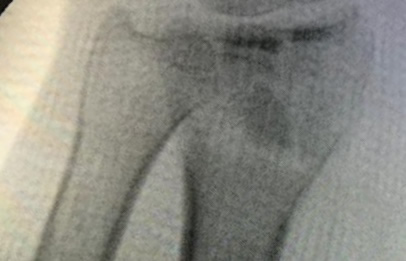

Cirugía de Muñeca y Mano

Los procedimientos más comunes en cirugía de la mano son aquellos destinados a reparar traumatismos, incluyendo lesiones de tendones, nervios, vasos sanguíneos, y articulaciones; huesos fracturados; y quemaduras, cortes, y otros daños de la piel.